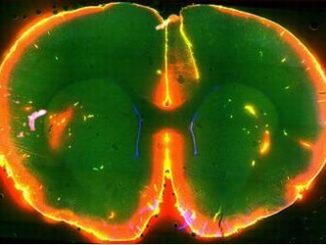

mouse brain

Brain ‘Cleans’ Itself of Toxins During Sleep

ROCHESTER, New York, October 18, 2013 (ENS) – Sleep clears the brain of toxins that have accumulated in the body during waking hours, American scientists have demonstrated for the first time. The results suggest a new role for sleep in health and disease. […]